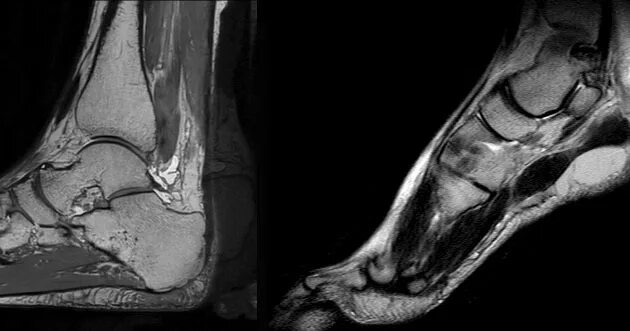

Синовит голеностопного таранного сустава